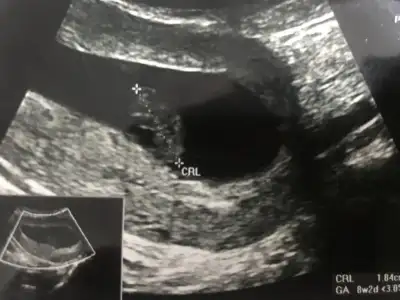

Kaç haftalık.usgler 11 12 13 haftalar olmalı sanki kız gibi emin değilim başka USG paylaşınbanada yorum yaparmisiniz ikra hnm

Canım bana da bakar mısın 7+3 karından bakıldı6-7 haftalık gebelikte bebek plasentaya çok yakın konumdadır ve elinizdeki vajinal görüntüde bebek sağdaysa erkek. Bu yöntem %97 doğrudur yazıyor sitede